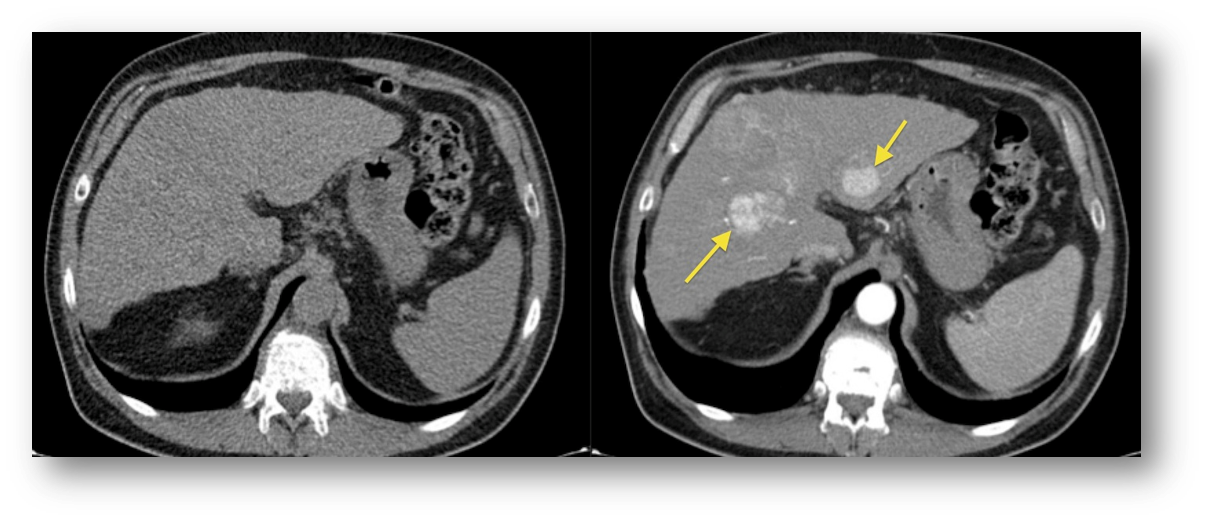

Q

what is the difference between these two pictures

A

the left is without contrast, the right is with contrast

20

metastatic lesion